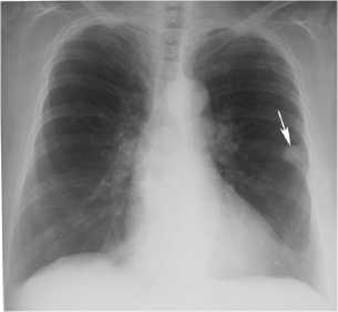

Мал. 122. Периферійний рак лівої легені (стрілка) на оглядовій рентгенограмі органів грудної клітки.

Периферійний рак виникає з епітелію слизової оболонки субсегментарних бронхів і бронхіол. Клінічні симптоми цієї форми раку залежать від розміщення пухлинного вузла по відношенню до грудної стінки та великих бронхів. Вростання пухлини в плевру спричинює біль у ділянці грудної клітки. Коли пухлина проникає у великий бронх, з’являється кашель, мокротиння, кровохаркання.

Х-променеве та КТ-дослідження виявляє периферійний рак у вигляді вузла або маси діаметром 2-4 см і більше, як правило, у верхніх частках легень, частіше справа. Важливими ознаками периферійного раку легені є: 1) неправильна куляста форма, що виявляється на КТ та рентгенологічному багатоосьовому дослідженні хворого (мал. 122, 123); 2) неоднорідна структура тіні пухлини, яка складається з окремих вузлів, що визначається на рентгенограмах, звичайних і комп’ютерних томограмах; 3) нерівні, горбисті, на окремих ділянках нечіткі, змазані контури тіні; 4) незмінена легенева тканина навколо тіні ракового вузла; 5) наявність в окремих випадках «доріжки» до кореня легені, зумовленої дрібними метастатичними висипаннями, або проростанням пухлини вздовж лімфатичних судин (раковий лімфангоїт); 6) стовщення плеври, спайки, зрощення, або плевральні випоти, які спостерігаються при близькому розміщенні пухлини до плеври; 7) порожнина неправильної форми з нерівними краями, без горизонтального рівня, яка з’ являється при розпаді пухлини і краще виявляється на комп’ютерній або лінійній томограмі (мал. 124, 125).